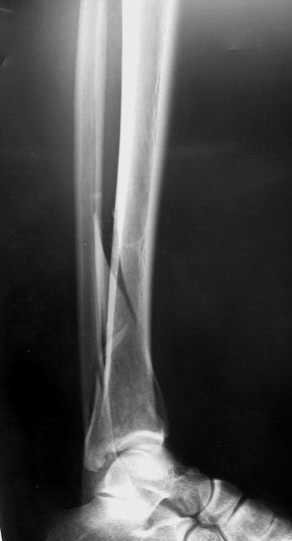

Глубокоуважаемые коллеги! Необходима ваша помощь.На консультацию обратился пациент 27 лет.

1,5 месяца назад при падении со скалы получил перелом пилона, лечился в районной больнице консервативно (циркулярная гипсовая повязка до средней 1/3 бедра). К нам попал только сегодня, сделали снимки и возник вопрос - делать ли что-то хирургически или уже пойти только на восстановительное лечение (продолжить иммобилизацию еще на 2-4 недели, потом разработка движений и т.п.)?Снимки прилагаю.

Уважаемые коллеги! Внутрисуставной перелом дистального конца б/б кости со смещением и подвывихом стопы должен был лечиться оперативно в раннем сроке.

Если судить по представленной рентгенограмме, то, с учетом давности травмы, операция уже вряд ли необходима. Я бы продолжил гипс и назначил хондропротекторы и витамины.

После 7 недельного консервативного лечения дистального эпи-метафиза, Pylon type (кстати неплохой сустав)перелома, вряд ли поможет операция, наложить гипс на 3 недели и начать разработку сустава, ледующие снимки подскажут время нагрузки на конечность.